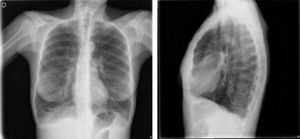

¿Qué pruebas complementarias habría que realizar?Es necesario realizar pruebas de laboratorio y de imagen torácica. En la analítica inicial destacó la aparición de 13400 leucocitos con desviación izquierda y sin eosinofilia, una hemoglobina de 18,0g/dl con hematocrito del 52,1% y una proteína C reactiva de 33,1mg/dl. En la radiografía de tórax no se observaron consolidaciones parenquimatosas ni derrame pleural, aunque sí alteraciones inespecíficas de la trama broncovascular bilateral y signos de hiperinsuflación pulmonar (fig. 1). Ante la insuficiencia respiratoria mantenida que obligó a escalar a mascarilla Ventimask® con fracción inspirada de oxígeno (FiO2) del 50% y 15 litros/minuto de oxígeno (O2) y un valor de dímero D elevado (1,39mg/l), se realizó una angio-tomografía computarizada (angio-TC) de tórax para descartar un tromboembolismo pulmonar. No se observaron defectos de repleción vascular, pero sí un extenso enfisema centroacinar de predominio en lóbulos superiores y bronquiectasias cilíndricas en ambas bases ocupadas por contenido mucoso, recibiendo tratamiento con amoxicilina más ácido clavulánico. La reacción en cadena de la polimerasa (PCR) para SARS-CoV-2 y gripe fueron negativas, pero positiva para rinovirus. Se determinó el valor de alfa-1-antitripsina, que estaba dentro de la normalidad (216mg/dl).